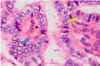

Know this image.

yeah.